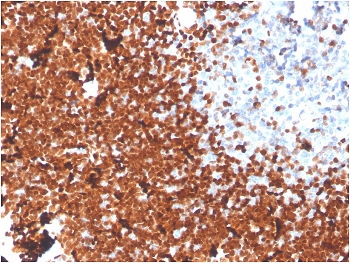

IHC staining of FFPE human thymus with TdT antibody. HIER: boil tissue sections in pH 9 10mM Tris with 1mM EDTA for 20 min and allow to cool before testing.